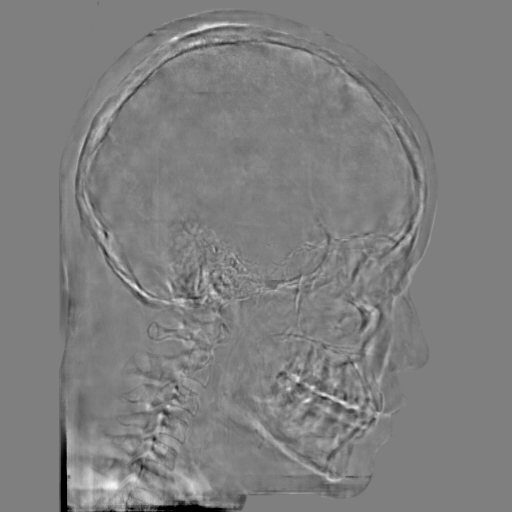

5.2 Head Data

Refer to caption

(a) Reference

(b) 0superscript00^{\circ} perspective

(c) (b)-(a)

7.80, 0.9093

Pix2pixGAN Prediction

(d) 0superscript00^{\circ} Cartesian

(e) 0&180superscript0superscript1800^{\circ}\&180^{\circ} Cartesian

(f) 0&180superscript0superscript1800^{\circ}\&180^{\circ} polar

6.06, 0.9249

2.99, 0.9820

2.07, 0.9842

Pix2pixGAN difference

(g) (d)-(a)

(h) (e)-(a)

(i) (f)-(a)

TransU-Net Prediction

(j) 0superscript00^{\circ} Cartesian

(k) 0&180superscript0superscript1800^{\circ}\&180^{\circ} Cartesian

(l) 0&180superscript0superscript1800^{\circ}\&180^{\circ} polar

6.45, 0.9356

2.36, 0.9864

3.65, 0.9734

TransU-Net Difference

(m) (j)-(a)

(n) (k)-(a)

(o) (l)-(a)

Figure 11: Perspective deformation learning in one exemplary patient case for cephalometric imaging. In (b), the left and right sides of the mandible do not overlap well, as indicated by the arrow. In (c), a scale bar of 2 mm is displayed (zoom in for better visualization), as 2 mm is the clinically acceptable precision for cephalometric landmark detection. In (e), (h) and (j), incorrect areas are marked by the red arrows.

The results of one exemplary patient for cephalometric imaging are displayed in Fig. 11. In the 0superscript00^{\circ} perspective projection image (Fig. 11(b)), because of perspective deformation, anatomical structures from the left and right sides do not overlap well, especially for the mandible as indicated by the red arrow in Fig. 11(b). It causes inaccuracy in determining the cephalometric landmark of the gonion. The difference of Fig. 11(b) to the reference Fig. 11(a) is displayed in Fig. 11(c). A scale bar of 2 mm is displayed in Fig. 11(c), as 2 mm is the clinically acceptable precision for cephalometric landmark detection. It is obvious that many anatomical structures in the 0superscript00^{\circ} perspective projection images have position shifts larger than 2 mm. In the prediction image (Fig. 11(d)) using a single 0superscript00^{\circ} view in Cartesian coordinates, perspective deformation is reduced to some degree, as displayed in the difference image Fig. 11(g). For example, the mandible region has less error. However, Fig. 11(g) also indicates that many bony structures still have deviations larger than 2 mm. The results of learning from dual complementary views in Cartesian and polar coordinates are displayed in Fig. 11(e) and Fig. 11(f), respectively. Both images have little perspective deformation, as revealed by their difference images in Fig. 11(h) and Fig. 11(i). Nevertheless, in Fig. 11(e), two dark regions are indicated by the two arrows, which are better visualized in the difference image Fig. 11(h). The results of TransU-Net are displayed in Figs. 11(j)-(o). In Fig. 11(m), the structures near the porion landmark are distorted, for example, the ear canal indicated by the arrow. Consistent with Pix2pixGAN, perspective deformation is largely reduced in the both TransU-Net prediction images using dual complementary views in Cartesian and polar coordinates.